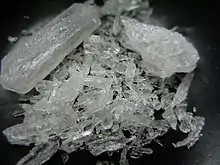

Methamphetamine is a chiral compound with two enantiomers, dextromethamphetamine and levomethamphetamine. At room temperature, the free base of methamphetamine is a clear and colorless liquid with an odor characteristic of geranium leaves.[12] It is soluble in diethyl ether and ethanol as well as miscible with chloroform.[12]

In contrast, the methamphetamine hydrochloride salt is odorless with a bitter taste.[12] It has a melting point between 170 and 175 °C (338 and 347 °F) and, at room temperature, occurs as white crystals or a white crystalline powder.[12] The hydrochloride salt is also freely soluble in ethanol and water.[12] The crystal structure of either enantiomer is monoclinic with P21 space group; at 90 K (−183.2 °C; −297.7 °F), it has lattice parameters a = 7.10 Å, b = 7.29 Å, c = 10.81 Å, and β = 97.29°.[153]